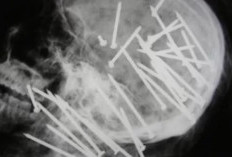

VIRAL! Foto Tengkorak Kepala Chen Liu Ada 34 Paku yang Tertancap, Apakah Asli atau Hasil AI?